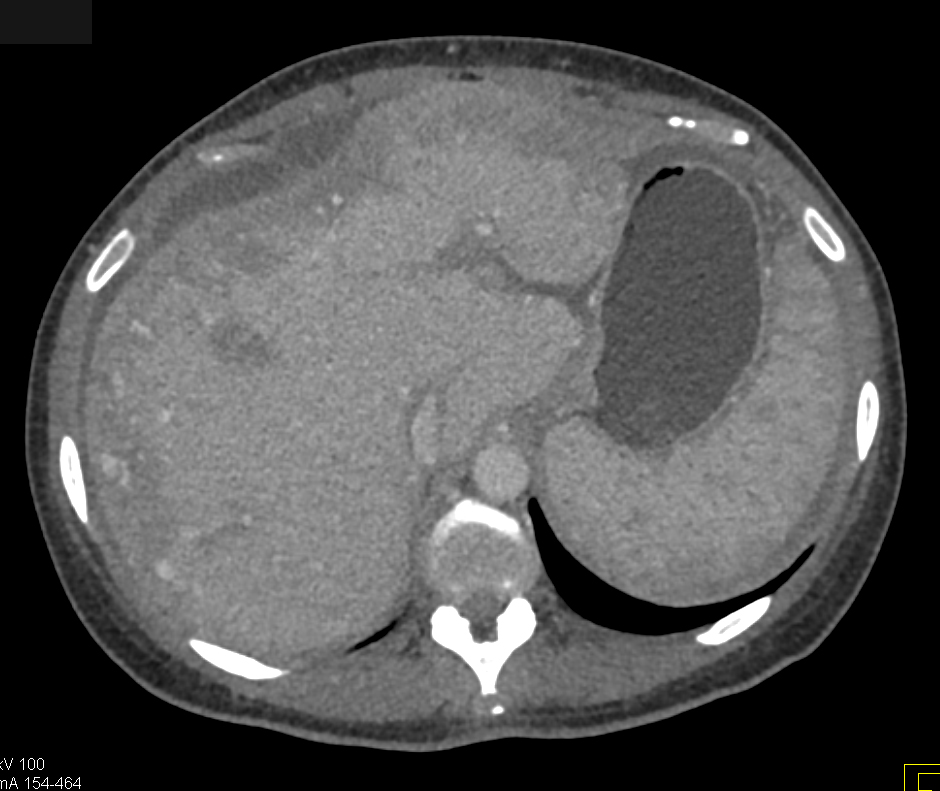

Diagnostic Case Quiz ❯ Anatomical Region Quiz: Liver

The best diagnosis in this case is?

hepatoma

cirrhosis

regenerating nodules

liver metastases